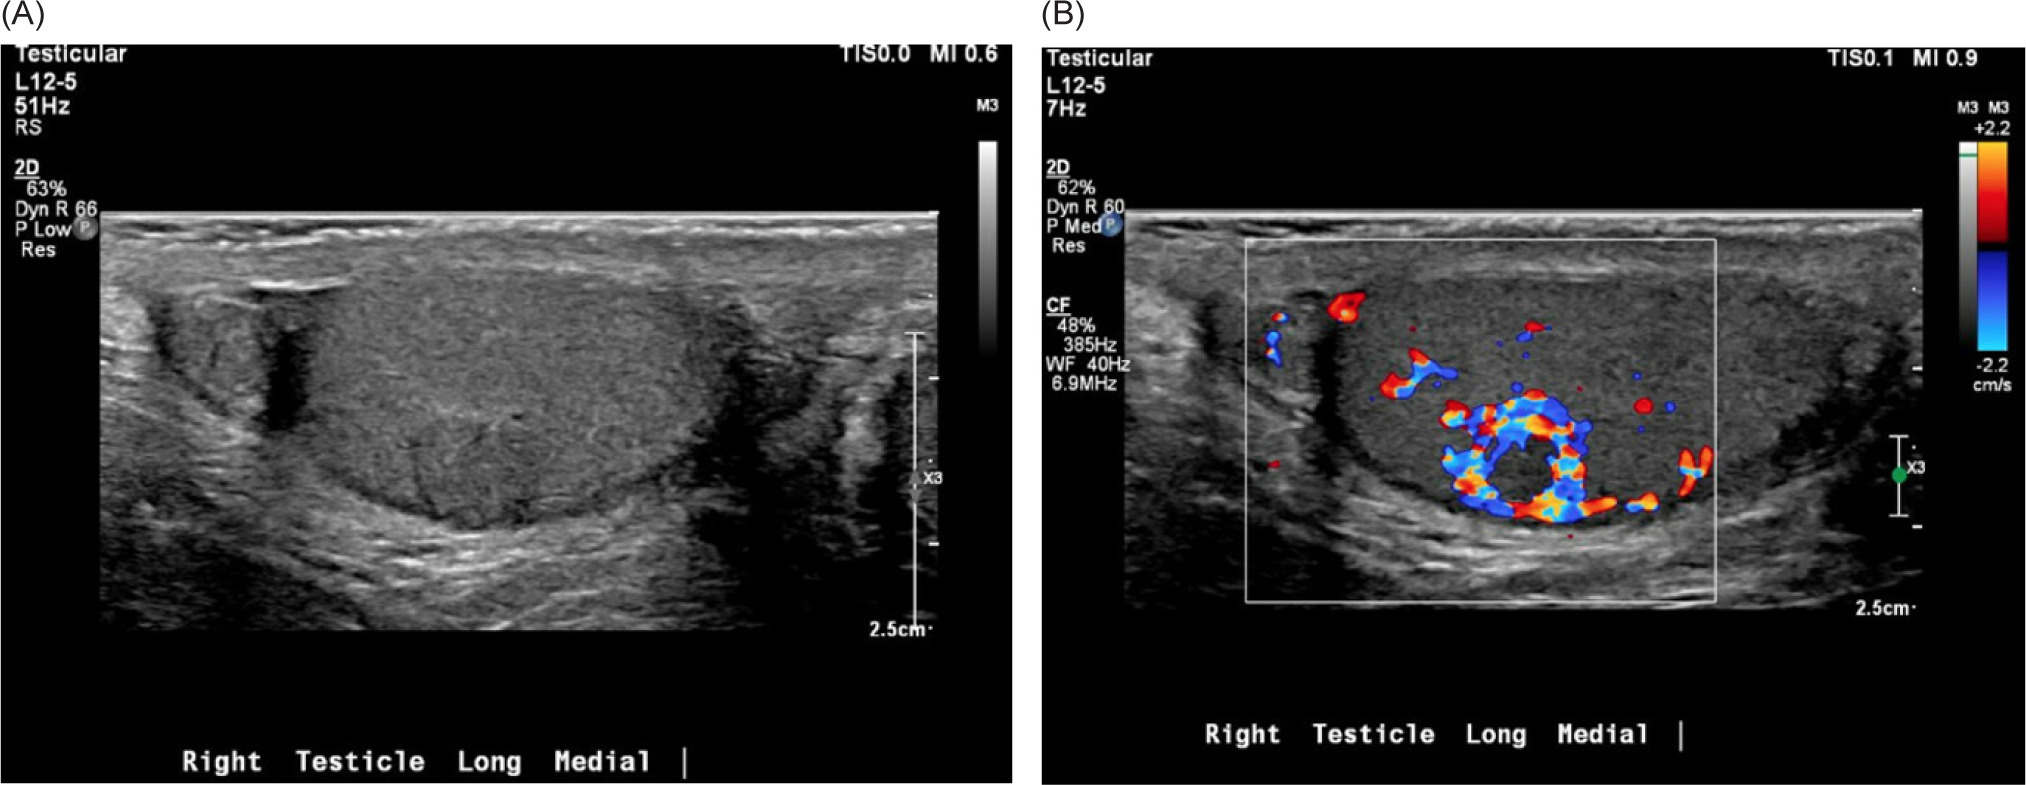

A PSMA–PET/CT scan was performed and was notable for a PET-avid right testicular mass (Figure 1). Subsequent scrotal ultrasound showed a solid, hypervascular 8 mm × 7 mm × 7 mm mass in the right testicle concerning for primary germ cell tumor (Figure 2). Serum tumor markers (AFP, LDH, and HCG) were obtained which were unremarkable. A right radical orchiectomy (Figure 3) was performed with final pathology demonstrating a metastatic clear cell RCC to the testis with lymphovascular invasion (Figure 4).

Figure 2: (A) Scrotal ultrasound demonstrating long view of the medial right testicle with echogenic, heterogeneous, and well-circumscribed mass. (B) Doppler ultrasound demonstrating hypervascularity of the previously characterized mass.